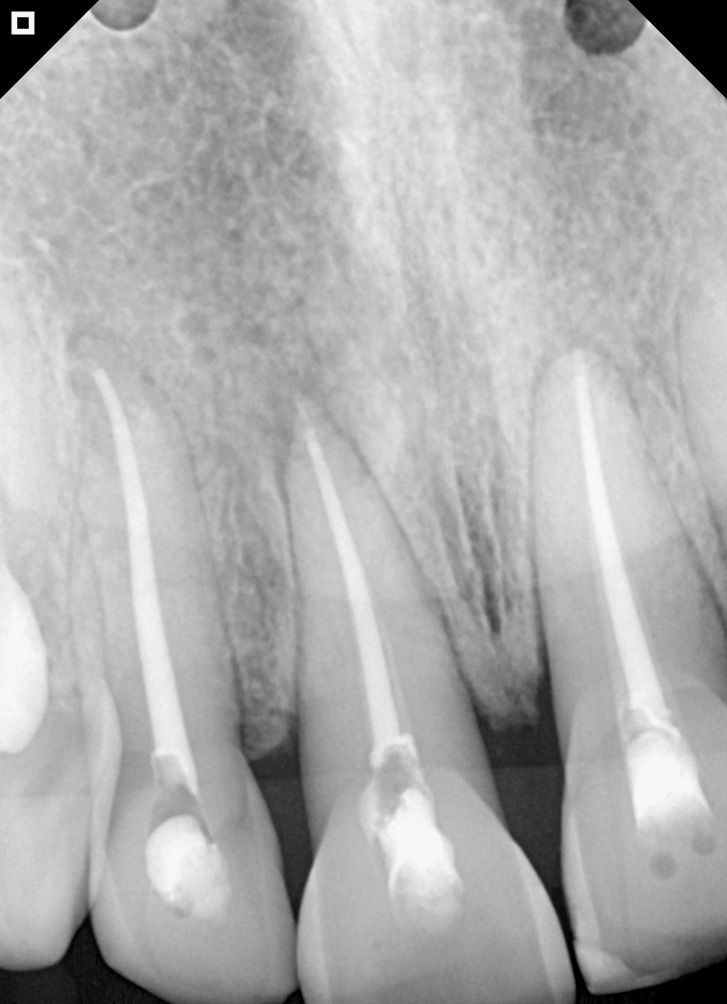

30-day follow-up radiography.